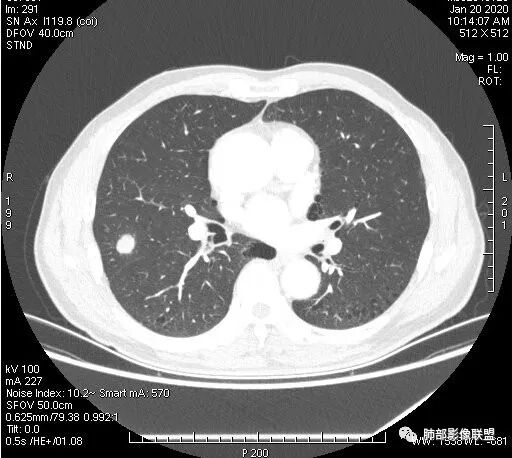

晨读:双肺胸膜下多发小气囊,大小不一,右肺结节,内部可见小空洞,洞壁光滑,厚薄不一,偏心性生长,近段血管束增粗,有分叶,毛刺(软),有晕征,平扫密度尚可,增强后不均匀强化,可见低密度坏死,及部分血管穿行,体检发现,考虑恶性:腺癌,鉴别炎性结节

有空泡征,实性部分密度均匀?强化均匀?

内部血管怎么样?

支气管?

支气管堵塞

支气管截断明显啊,南大不指出,我没看出来。

右肺上叶结节,周围毛刺明显,其内有小炮征,分叶,强化中度,其内可见坏死,支气管有截断,考虑腺癌,鳞癌待排。病灶的上缘有一个小支气管进入,然后截断了

晨读:男,67岁,体检发现右肺结节。近圆形,支气管及伴行血管进入结节,进入结节后支气管堵塞,血管走形尚自然,结节内血管边缘凹凸不平。远端边缘见毛刺(软毛刺?)及分叶。见胸膜牵拉。实变中见空洞。整体膨胀感不明显。考虑炎性肉芽肿可能,隐球菌病可能性大。注意鉴别鳞癌、结核。

这里支气管是进入到结节内以后才断的

这个大部分边缘稍微偏平直一点,血管走行非常自然,包括里面的空泡征样的,影子很干净,边界很光滑,都是些炎性特点。